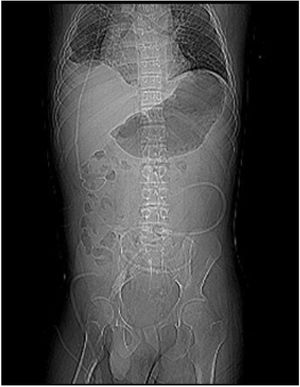

We report the experience of a 20-year-old patient, with myelomeningocele and hydrocephalus at birth, who underwent surgery for implantation of ventriculoperitoneal shunt (DVP) (Fig. 1). He presented with neurogenic bladder and bilateral hydronephrosis, multiple episodes of urinary tract infection, and urethral stricture due to prolonged use of an indwelling urinary catheter. He finally developed CKD and started RRT (hemodialysis) at the age of 15.